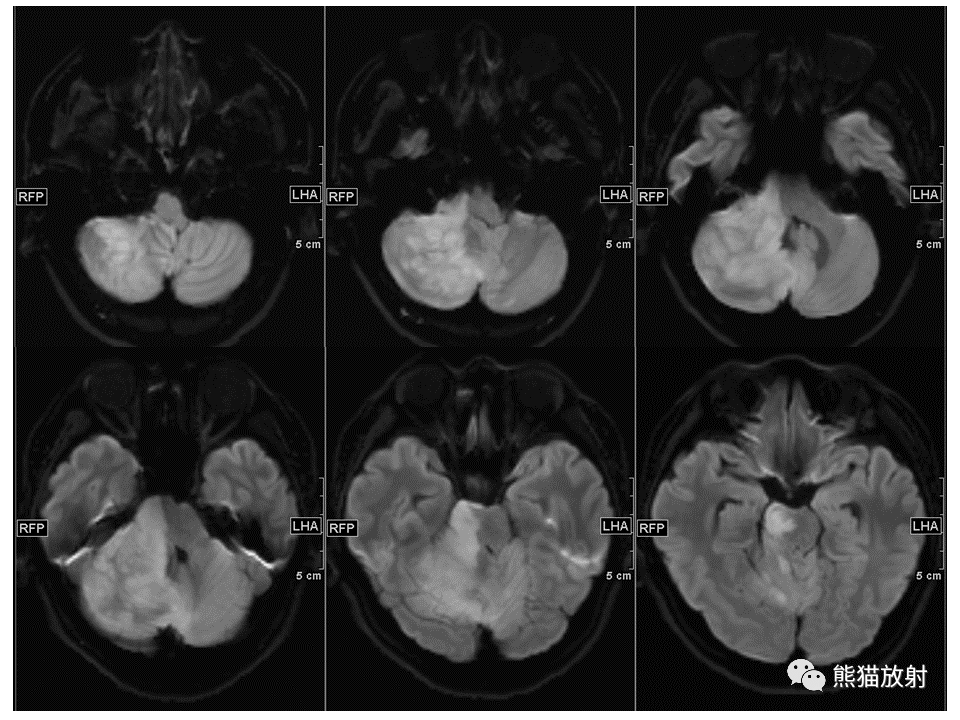

【PPT】小脑发育不良性神经节细胞瘤 VS 成人型髓母细胞瘤-1